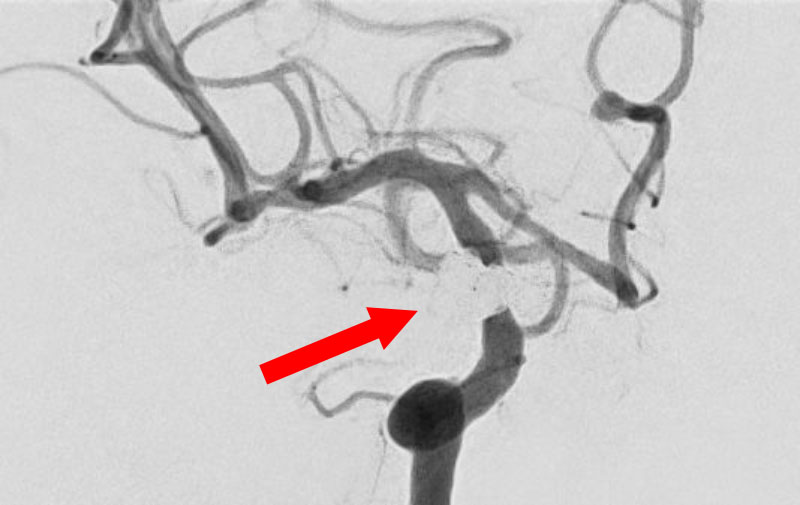

くも膜下出血

左中大脳動脈瘤破裂

40代

救急外来

No.1596 手術前